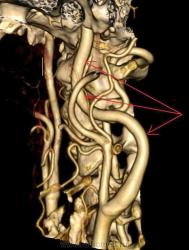

Персистирующая примитивная тройничная артерия.

Мужчина 63 лет с жалобами на опущение верхнего века справа. Направлен на КТ-ангиографию для исключения аневризмы в области сифона правой внутренней сонной артерии.

При КТА отмечается гипоплазия вертебральных артерий, больше выраженная справа. Основная артерия на большем протяжении не развита, дистальная часть ее питается из расширенной примитивной тройничной артерии, отходящей от проксимальных отделов сифона правой внутренней сонной артерии. Кроме этого правая задняя мозговая артерия отходит от супраклиноидного отдела внутренней сонной артерии – задняя трифуркация. Слева отсутствует задняя соединительная артерия.

Таким образом кровоснабжение вертебро-базиллярного бассейна осуществляется из правой внутренней сонной артерии.

Голубые стрелки – вертебральные артерии.

Красные – задние мозговые.

Зеленые – тройничная артерия.

Желтые – основная артерия.

Черные – сифон внутренней сонной.